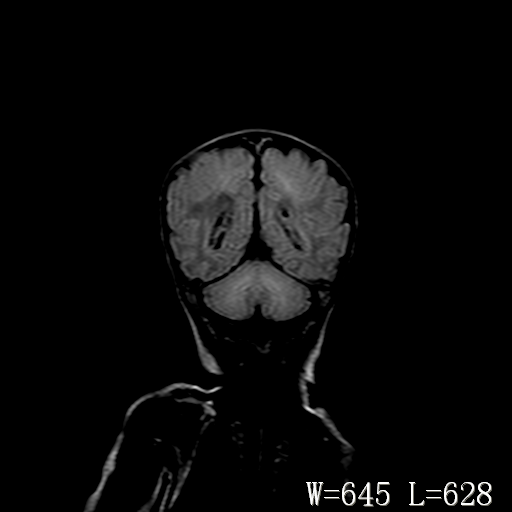

男,4天,发复抽搐1天。

新生儿正常颅脑

hie?

脑干形态欠规则,信号增高,不知怎么解释?

脑干背侧面t1高信号是,新生儿正常已经髓鞘化好的部位